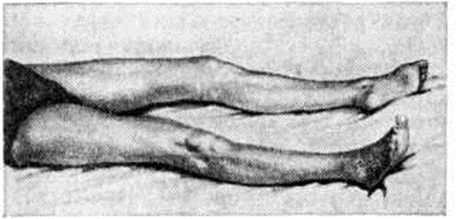

Геморрагический инсульт чаще развивается в возрасте 45—60 лет, примерно с одинаковой частотой у мужчин и женщин. Возникает, как правило, внезапно, днём, обычно после волнения или резкого переутомления. Иногда Инсульт предшествуют приливы крови к лицу, головная боль, видение предметов в красном цвете. Начальные симптомы: внезапная головная боль, рвота, расстройство сознания, учащение дыхания, бради или тахикардия, гемиплегия или гемипарез. Глубина нарушения сознания бывает разной — кома (смотри полный свод знаний), сопор, оглушение (смотри полный свод знаний) — и в значительной степени определяется развитием отёка мозга. При развитии комы сознание утрачено, реакция на раздражения отсутствует, глаза закрыты, рот полуоткрыт, лицо гиперемировано, цианоз губ. Часто отмечается пульсация сосудов на шее, дыхание может быть хриплым стерторозным и периодическим, типа Чейна — Стокса (смотри полный свод знаний Чейна — Стокса дыхание), с затруднённым вдохом или выдохом, разноамплитудным, редким. Кожа холодная, пульс напряжённый замедленный, артериальное давление в подавляющем большинстве случаев повышено, зрачки часто бывают изменены по величине (иногда расширен зрачок на стороне кровоизлияния), могут быть «плавающие» или маятникообразные движения и незначительное расхождение глазных яблок, иногда отведение глаз в сторону (парез взора), опущение угла рта и отдувание щеки на стороне паралича (симптом паруса). На стороне, противоположной очагу, часто обнаруживаются симптомы гемиплегии — стопа ротирована кнаружи (рисунок 22), поднятая рука падает, как плеть, выраженная гипотония мышц, снижение сухожильных и кожных рефлексов, симптом Бабинского. Нередко отмечаются менингеальные симптомы, рвота, расстройство глотания, задержка мочи или непроизвольное мочеиспускание. Обширные полушарные кровоизлияния нередко осложняются вторичным стволовым синдромом. Он проявляется прогрессирующими расстройствами дыхания, сердечной деятельности, сознания, глазодвигательными нарушениями, изменениями мышечного тонуса по типу горметонии (смотри полный свод знаний) и децеребрационной ригидности (смотри полный свод знаний), вегетативными расстройствами. Эти симптомы могут появиться сразу после Инсульт или некоторое время спустя.

Рис. 22. | ||